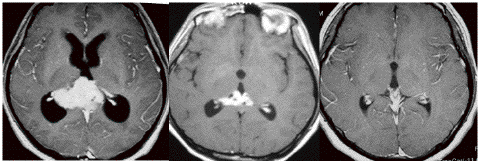

ICE化学療法投与開始から数日で小さくなります

この例は古いので第3脳室開窓術 ETV をしていません。左はICE化学療法前。中央は9日後。右は25日後です。閉塞性水頭症があっても1週間くらいで中脳水道が通って水頭症は改善します。ジャーミノーマであれば,ICE化学療法1コースでかなり縮小するはずです。このような顕著な効果がない時には,逆にジャーミノーマ以外の胚細胞腫瘍が混在していると考えた方がいいでしょう。多くは奇形腫の混在です。

2000年頃の例です。閉塞性水頭症を併発する松果体部germinoma:左のMRIは発症時のものです。定位的生検術で確定診断して脳室ドレナージを留置しました。1コースのICE化学療法直後,生検術から6日目のMRI(中央)では腫瘍はほぼ消失し,水頭症は改善したのでドレナージを抜去しました。4コースの化学療法後(右側)に24Gyの全脳室照射を加えました。